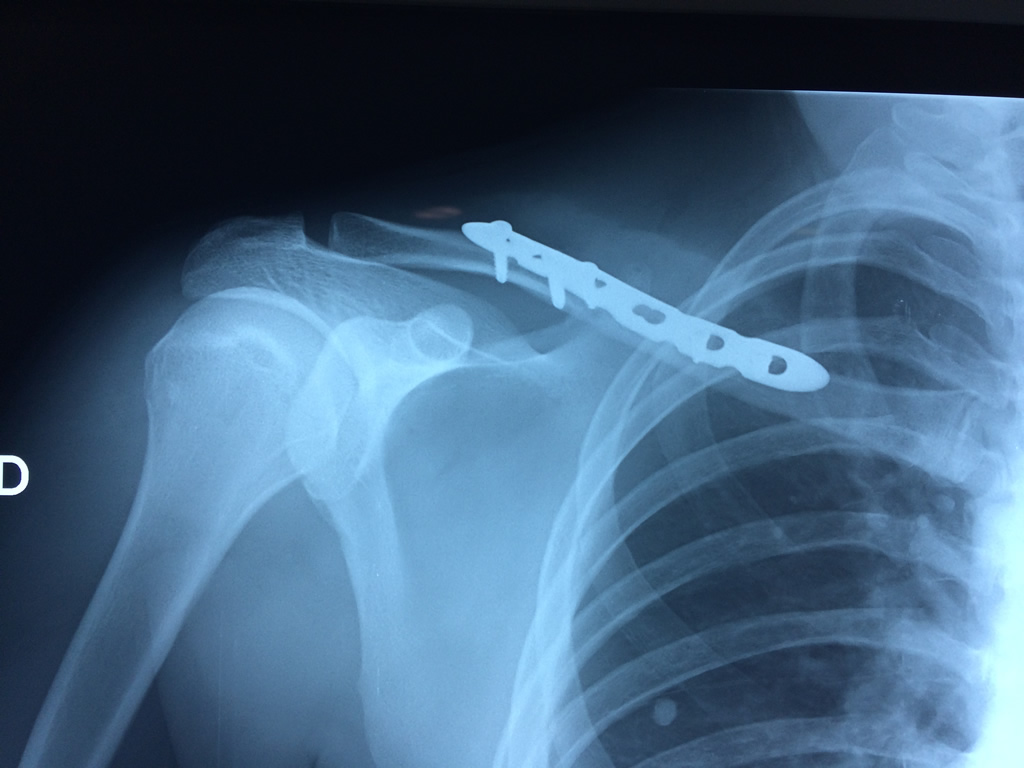

La clavícula es un hueso largo, con forma de "S" itálica, situado en la parte anterosuperior del tórax. Junto con la escápula forman la cintura escapular. Se puede palpar por toda su longitud y se extiende del esternón al acromion de la escápula, siguiendo una dirección oblicua lateral y posterior.

Se considera el único medio de unión entre el miembro superior y el tórax. A pesar de su aspecto, similar al de un hueso largo, posee una estructura semejante a la de un hueso plano, ya que carece de epífisis y de diáfisis, lo que la harían entrar dentro de la clasificación de hueso largo. Carece de un canal medular propiamente dicho.